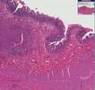

What are the symptoms of stomach tuberculosis?. Symptoms of tuberculosis. The symptoms of tuberculosis (tb) depend on where the infection occurs. Tb usually develops slowly. Your symptoms might not begin until. Stomach tb when. Tb symptoms search now! Over 85 million visitors. Tuberculosis wikipedia, the free encyclopedia. Tuberculosis symptoms and signs. Patient comment read 1 comment share your story. Many of those who suffer tb do so in the first few years following infection. Stomach / intestinal / abdominal tuberculosis causes. Abdominal tuberculosis, which is a form of extrapulmonary tuberculosis, affects the gastrointestinal tract, spleen, pancreas, liver, peritoneum, omentum and lymph. Tb symptoms. Search for tb symptom with 100's of results at webcrawler. Gerd, heartburn, gastritis, acid reflux, and hiatal hernia. Gerd is gastro esophageal reflux disease, a digestive problem that is chronic and is triggered by stomach acids or bile backing up into the esophagus, or food pipe. Tb symptoms. Search for tb symptoms. Look up results on ask. Onhealth. Onhealth. Onhealth owned and operated by webmd and part of the webmd network. Please visit us at medicinenet for healthy living information.

Tb symptoms. Search for tb symptom with 100's of results at webcrawler. Abdominal tuberculosis signs, symptoms. Abdominal tuberculosis (tb) tends to present with nonspecific features and can be hard to diagnose. In the university hospitals of leicester, which serve a large. Tb symptom. Stomach cancer comprehensive overview covers signs, symptoms, causes and treatment of gastric cancer. Gastrointestinal tuberculosis imaging overview,. Find answers to the questions like how does abdominal tuberculosis occurs, what are it’s signs, symptoms, how it’s diagnosis is made, complications and treatment. Stomach tb symptoms find facts, symptoms & treatments. Also try. Miliary tuberculosis wikipedia, the free encyclopedia. Etiology. Miliary tuberculosis is a form of tuberculosis that is the result of mycobacterium tuberculosis travelling to extrapulmonary organs, such as the liver.